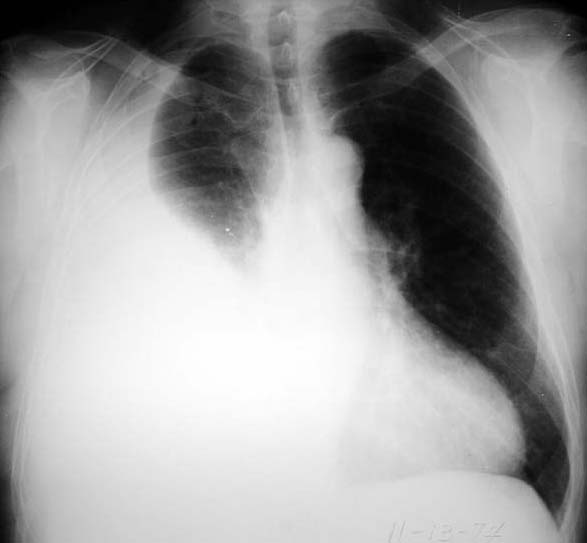

weekly clinical round for undergraduate from 8 to 11 AM during which interpretation of CHEST X rays was done for all cases of cardiothoracic surgery, gived by 2 staf member for 3 months